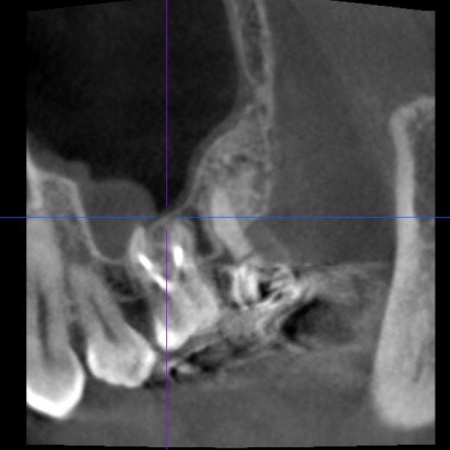

| 診断 | 口腔内を拝見し、レントゲンとCT撮影による詳しい検査を行った結果、左上奥歯の歯根内に細菌感染が起きており、炎症が歯根の先から鼻の横にある空洞「上顎洞(じょうがくどう)」にまで広がっていることがわかりました。

これは、歯性上顎洞炎(しせいじょうがくどうえん)と呼ばれる病気で、鼻づまりや鼻水、膿のにおいがするなどの症状があらわれることがあります。 また、このまま放置すると感染が周囲に広がり、炎症がさらに強くなったり歯を残すことが難しくなったりするリスクが高まります。 以上のことから、細菌に感染した部位を取り除き、歯の温存を目指す治療が必要だと診断しました。 |

| 行ったご提案・治療内容 | 歯性上顎洞炎を改善するためには、原因となっている歯根内部の細菌をできるだけ除去する必要があります。 また、患者様は「できるだけ歯を残して治したい」と希望されていたことから、精密根管治療を提案しました。 精密根管治療ではマイクロスコープ(歯科用高倍率顕微鏡)を使用し、肉眼では確認が難しい部分を拡大しながら治療を行います。これにより、複雑な根管内部や細かな感染部位まで確認できるため、より精密な処置が可能です。 一方で、根管の形態や感染の程度によっては治療が複数回に及ぶ場合があること、また根管治療を行っても上顎洞炎の改善がみられない場合には、外科的処置や抜歯を検討する必要があることもお伝えしています。 患者様には以上の内容をしっかりとご理解いただいたうえで、治療に同意いただきました。 まずは、左上奥歯に装着されていた既存の詰め物を取り外し、根管内部を確認します。 根管内部の洗浄と消毒が完了したら、根管の内部を密封する処置を行います。 最後にレントゲン撮影を行い、根管がしっかりと封鎖されていることを確認して、治療を終了しています。 |